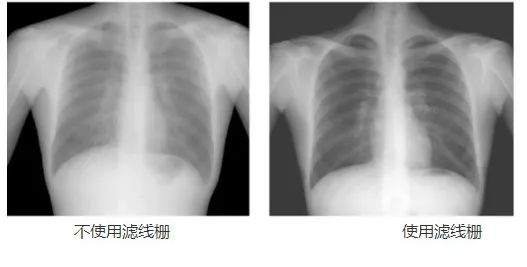

動態(tài)DR工作中的常用部件——濾線柵,可以幫助過濾散射線,降低灰霧度,提高對比度,從而提高成像質量